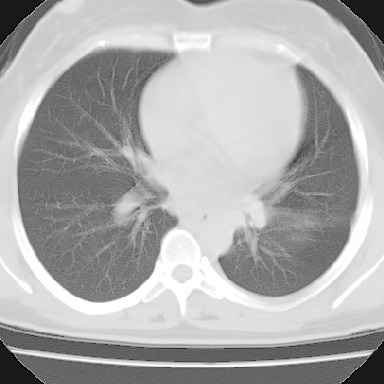

左下肺肿块影,内可以见小泡征,并见厚壁空洞形成,洞内缘凹凸不平,可见壁结节。靠近胸膜侧可见胸膜凹陷征。左侧胸腔内可见少量低密度积液影。双肺可见多发性小结节影。

考虑:左下肺癌性空洞伴两肺转移

偏心性厚壁空洞,壁结节,胸膜肥厚粘连,双肺多发性小结节灶。这么多典型征象,即使错了也错的有道理!

病灶与临床特点:1 位于下肺外围.2 与胸膜关系密切并明显胸膜反应.3 空洞内壁虽见壁结节,但还是较光滑.4 病灶周围明显渗出.5 另肺内多发小结节.6 临床症状轻,发病时间短.综合考虑:肺内特殊感染(霉菌感染).